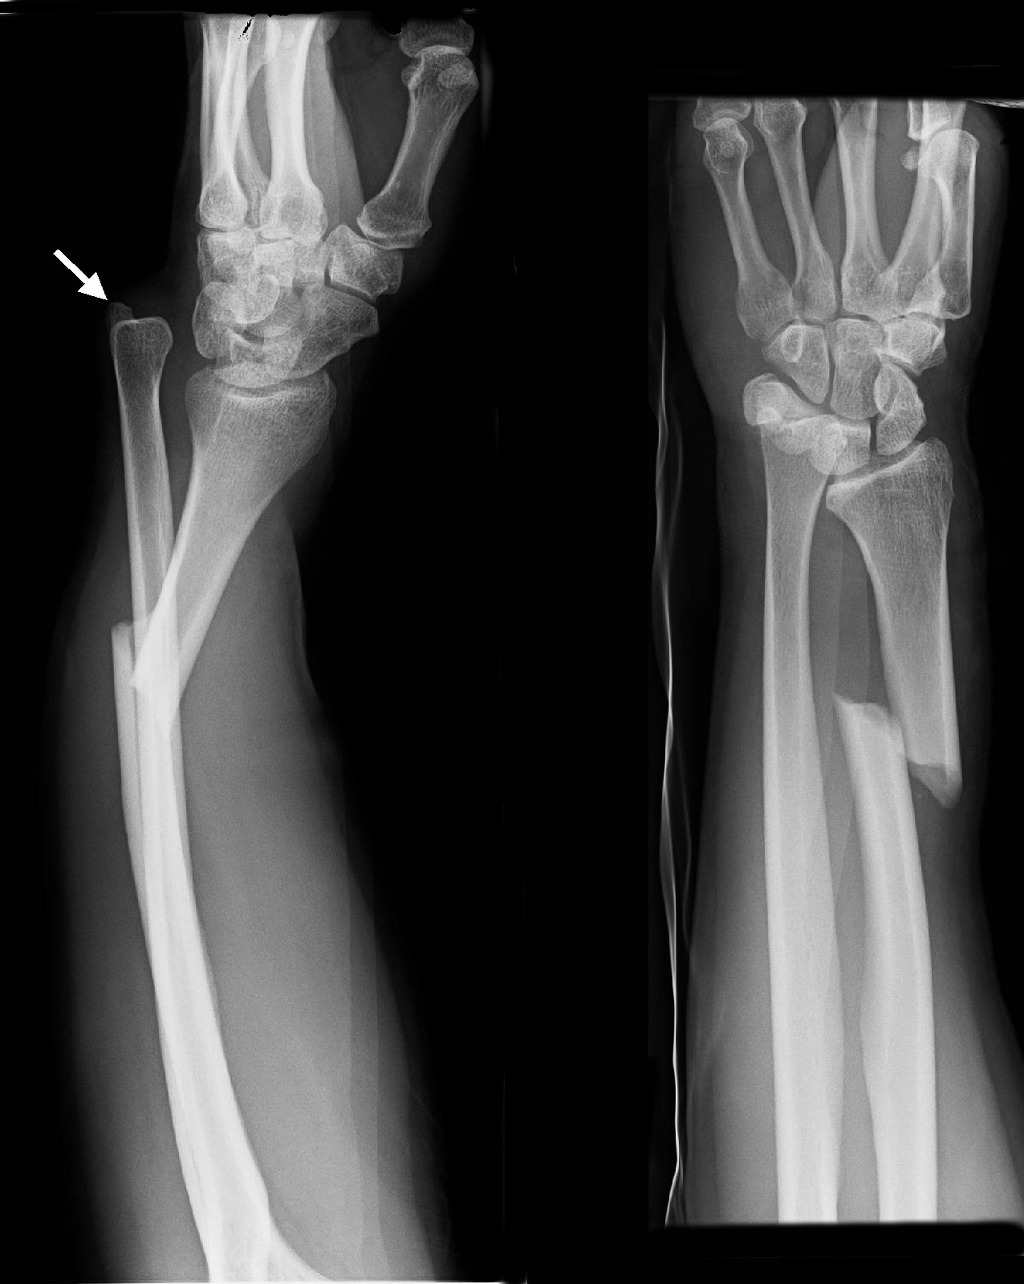

13. 갈레아찌 골절(Galeazzi fracutre)과 연관된 현상에 대해 기술하라.

갈레아찌 골절(Galeazzi fracutre)은 원위 요척관절 탈구/아탈구와 동반된 원위 요골 골절을 말한다. 갈레아찌 골절(Galeazzi fracutre)은 1935년에 명명되었다.

갈레아찌 골절 (이미지 출처 : http://en.wikipedia.org/wiki/Galeazzi_fracture)